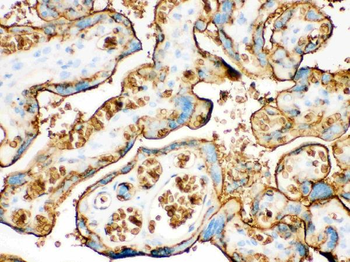

100 μg, 10 μg - Anti-Glucose Transporter GLUT1/SLC2A1 Antibody [orb259612]

FC, ICC, IF, IHC, IHC-Fr, WB

Human, Mouse, Rat

Rabbit

Polyclonal

Unconjugated